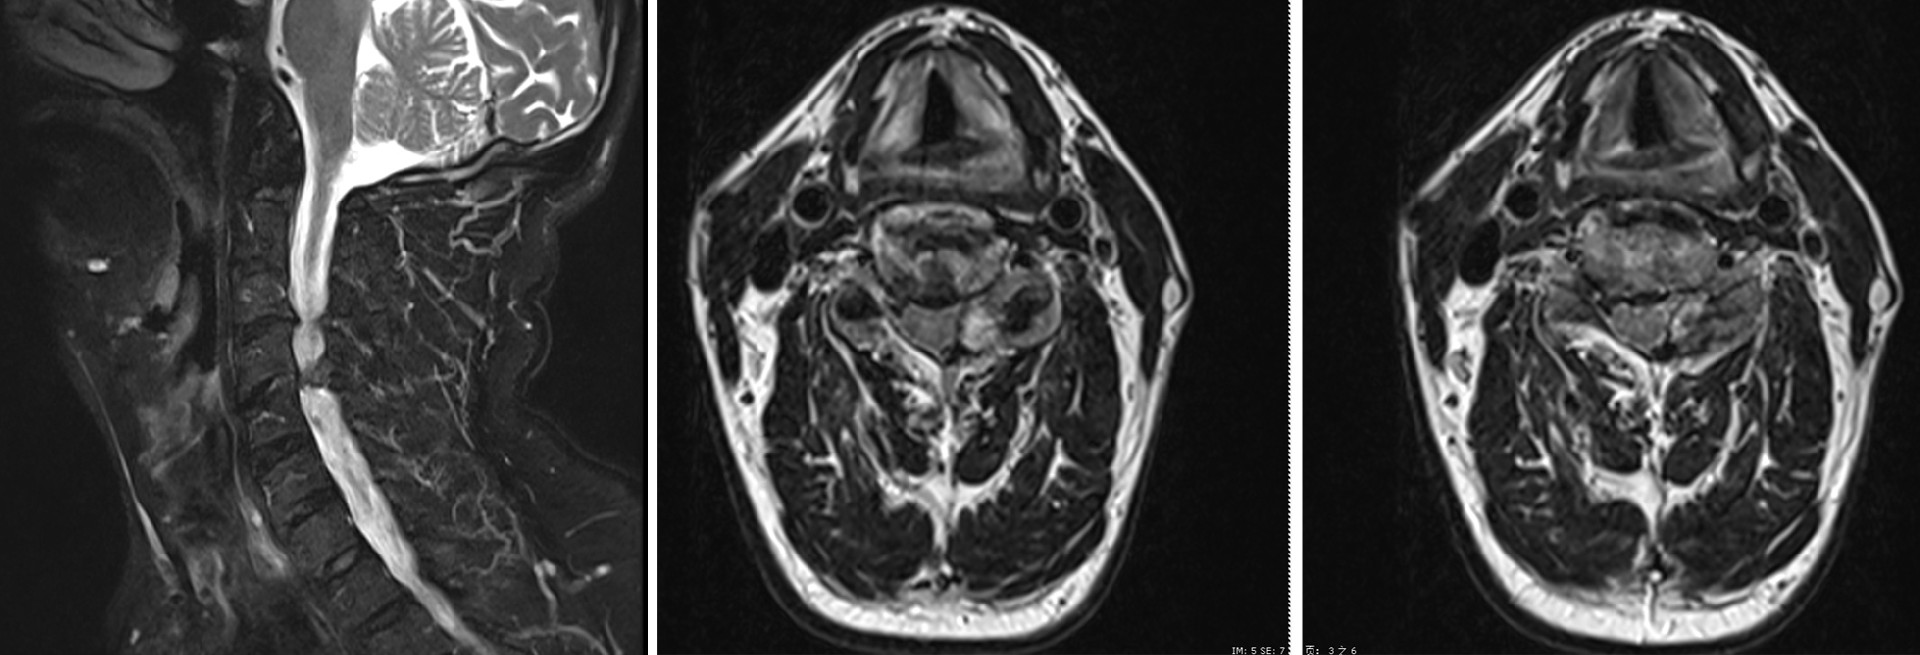

患者,男,61歲,頸肩疼痛及雙上肢麻木持續兩月余,并逐漸加劇,嚴重影響日常生活質量,來我院就診。經詳細門診檢查,特別是頸椎MRI精確診斷,明確患者的病因:C3/4水平椎管狹窄伴C4/5水平左側椎管內占位性病變。

術前MRI圖像